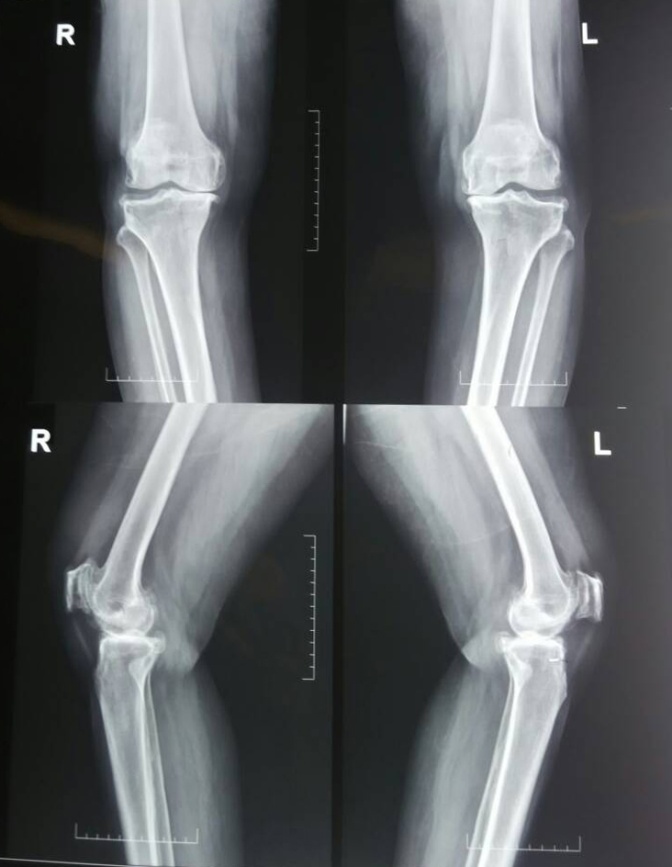

S-adenosyl methionine-Before treatment

S-adenosyl methionine-After treatment

X-Ray 3: The anteroposteiror and lateral view of the knee joint before and after treatment with S-adenosyl methionine

X-ray 3 shows the knee joint surface before and after treatment of S-adenosyl methionine. Pre-treatment X-ray shows mild narrowing of medial intercondylar joint space with subchondral sclerosis and minimal osteophytes. Femoropatellar joint joint space appears narrowed with retropatellar osteophytes. Post-treatment X-ray shows no significant radiological changes observed in the affected knee joint even after 12 w of treatment with S-adenosyl methionine.